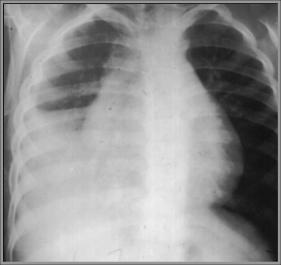

Strep pneumonia